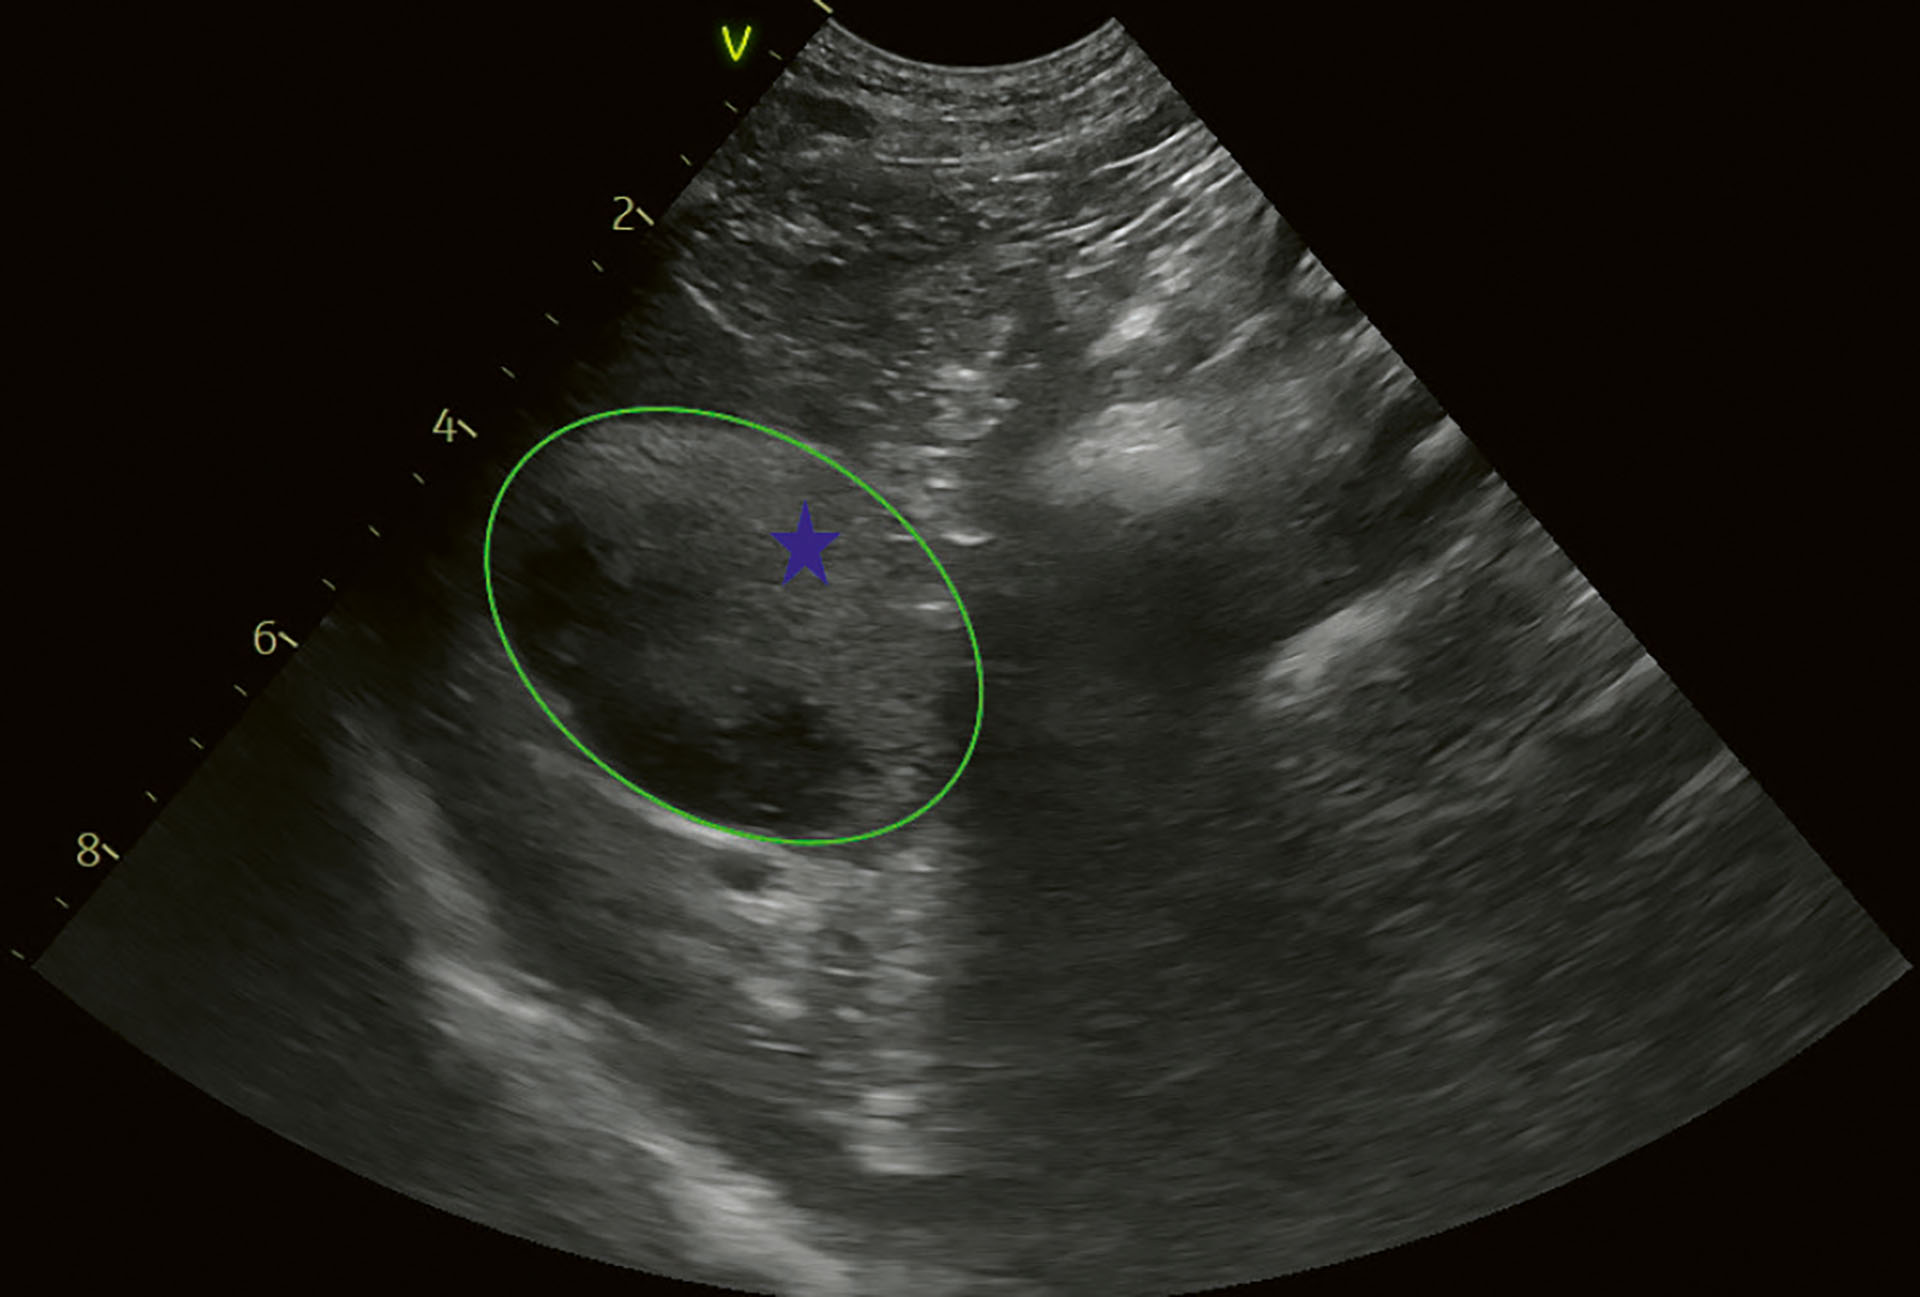

Det ble tatt blodprøver for hematologiske og biokjemiske analyser uten avvikende resultater. Ultralyd av buk viste at leveren hadde et homogent utseende. Det var ingen endring i ekkogenisitet i levervevet rundt galleblæren. Galleblæren hadde en hyperekkoisk masse som var lite bevegelig og som dekket mer enn 75 % av galleblærens volum. Galleblærens vegg hadde normalt utseende, med en tynn hyperekkoisk linje, uten tegn til fortykkelse. Galleblærens volum ble vurdert til å være forstørret. Den hyperekkoiske massen innerst mot galleblærens vegg var ubevegelig (Figur 8). Ultralyd av øvrige bukorganer var uten anmerkning.

Figur 8. Kasus 2. Tverrsnitt av galleblære. Det er mer enn 75 % av galleblærens volum som er dekket av ekkoisk innhold. Det er delvis mobilt, men innholdet nærmest veggen kunne ikke beveges. Blå stjerne indikerer ekkoisk innhold. Grønn ring indikerer galleblærens kant.

Foto: Anja B. Pedersen

Basert på funnene ved ultralydundersøkelsen ble pasienten diagnostisert med GBM grad 1 (7).